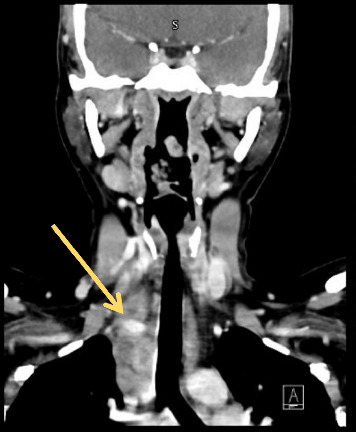

结核(TB),由结核分枝杆菌引起,主要影响肺部,但可以涉及几乎任何器官系统,表现为肺外结核。虽然结核病相关的高凝性和静脉血栓栓塞是公认的,但这种表现仍然不常见,诊断上具有挑战性,特别是在没有经典症状的情况下。病例介绍:我们报告一个24岁的免疫功能正常的女性谁最初提出无痛右侧颈部肿胀。影像显示右侧颈内静脉(IJV)出现急性血栓,原因不明。进一步检查显示纵隔淋巴结肿大坏死,怀疑为淋巴瘤。然而,患者后来出现癫痫发作,随后的神经影像学显示多发性颅内环增强病变。最终,纵隔镜淋巴结活检证实坏死性肉芽肿性炎症,结核聚合酶链反应(PCR)阳性,与弥散性结核累及血管和中枢神经系统一致。患者开始接受抗结核治疗、抗凝治疗和辅助皮质类固醇治疗,并安排多学科随访。讨论:本病例强调了结核病引起的高凝血性是孤立静脉血栓形成的潜在原因,并强调了结核病模拟恶性肿瘤时的诊断挑战。它还强调了即使在没有肺部症状的情况下,在鉴别诊断不明原因血栓形成和颅内病变时考虑结核病的重要性。结论:临床医生应在非典型血栓形成事件中保持对肺外结核的高度怀疑。早期组织诊断和多学科方法是有效管理和良好结果的关键。

Introduction: Tuberculosis (TB), caused by Mycobacterium tuberculosis, primarily affects the lungs but can involve virtually any organ system, manifesting as extrapulmonary TB. While TB-related hypercoagulability and venous thromboembolism are recognized, such presentations remain uncommon and diagnostically challenging, especially in the absence of classical symptoms. Case Presentation: We report the case of a 24-year-old immunocompetent female who initially presented with painless right-sided neck swelling. Imaging revealed an acute thrombus in the right internal jugular vein (IJV), with no clear underlying cause. Further evaluation showed enlarged necrotic mediastinal lymph nodes, raising suspicion for lymphoma. However, the patient later developed a seizure episode, and subsequent neuroimaging revealed multiple intracranial ring-enhancing lesions. Ultimately, mediastinoscopic lymph node biopsy confirmed necrotizing granulomatous inflammation, with a positive TB polymerase chain reaction (PCR), consistent with disseminated TB involving both vascular and central nervous systems. The patient was started on antitubercular therapy, anticoagulation, and adjunctive corticosteroids, with multidisciplinary follow-up arranged. Discussion: This case highlights TB-induced hypercoagulability as a potential cause of isolated venous thrombosis and underscores the diagnostic challenges when TB mimics malignancy. It also emphasizes the importance of considering TB in the differential diagnosis of unexplained thrombosis and intracranial lesions, even in the absence of pulmonary symptoms. Conclusion: Clinicians should maintain a high index of suspicion for extrapulmonary TB in atypical thrombotic events. Early tissue diagnosis and a multidisciplinary approach are key to effective management and favorable outcomes.